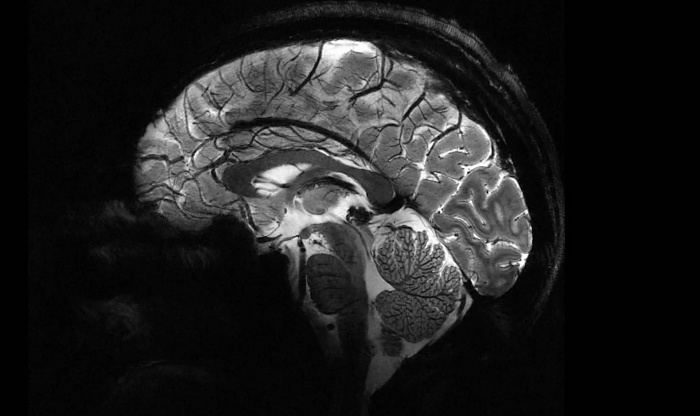

Во Франции разработан самый мощный в мире МРТ-аппарат Iseult — он способен обеспечить напряженность поля на уровне 11,7 Тесла. Это в несколько раз превосходит возможности массово применяемых МРТ-аппаратов в современных клиниках.

Главным отличием Iseult является возможность сканирования мозга в намного более высоком разрешении. Всего за 240 секунд он способен сделать снимки человеческого мозга в виде 1-миллиметровых срезов. Обычный МРТ для получения таких результатов потребует 2 часов неподвижного нахождения пациента внутри.

Несколькими годами ранее Iseult испытывался на тыквах, сейчас его протестировали на 20 добровольцах. Полученные изображения раскрывают весь потенциал технологии МРТ и позволяют лучше понять, как работает мозг. При этом, сверхмощный томограф может быть полезен не только ученым, но и медикам. С его помощью можно изучать и диагностировать такие нейродегенеративные недуги, как болезни Паркинсона и Альцгеймера.